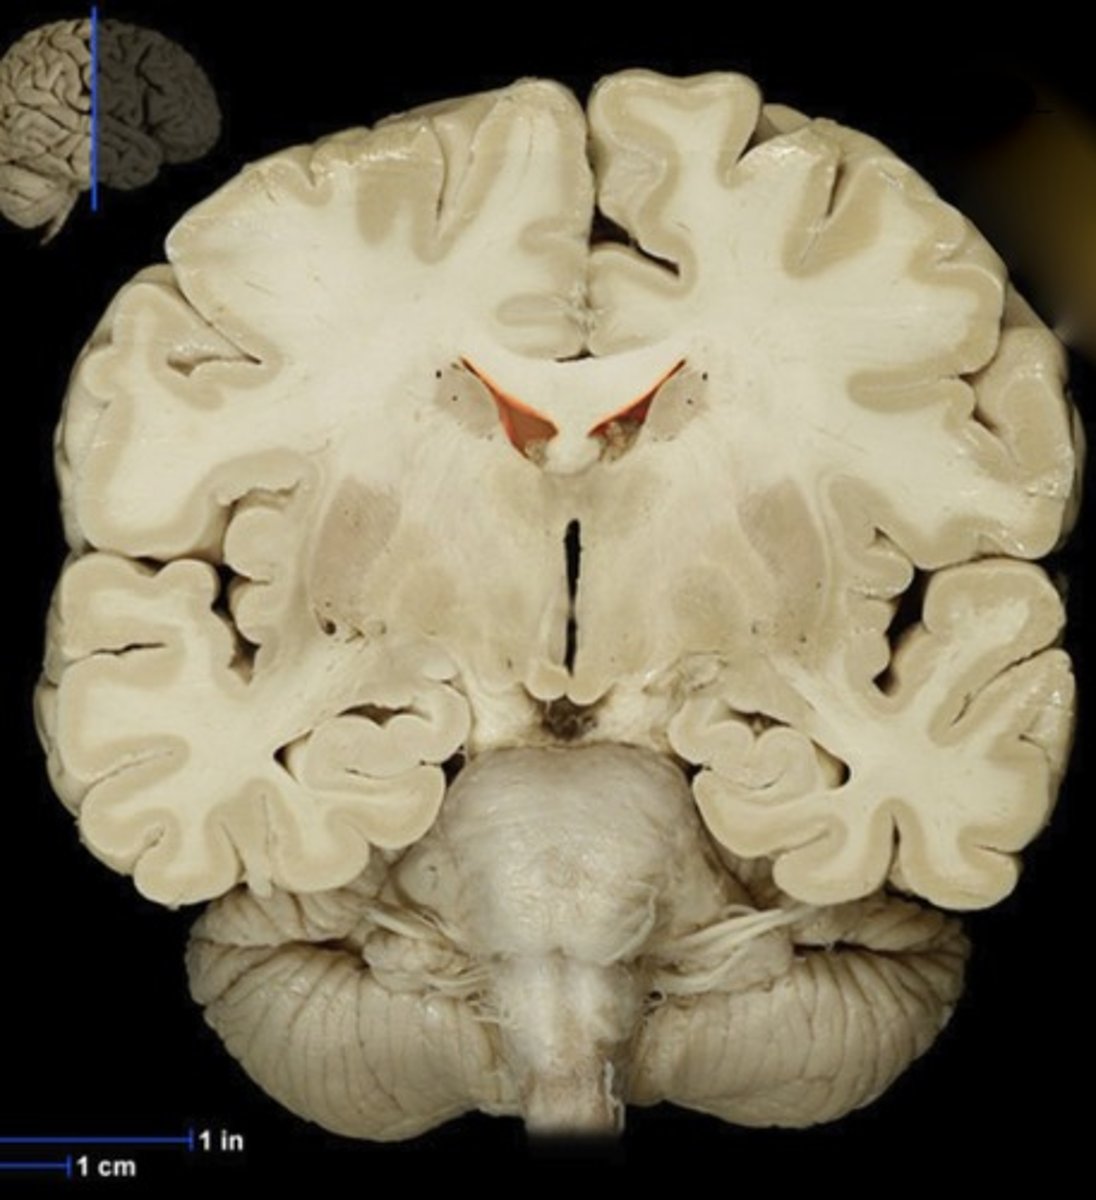

Caudate Nucleus

Name this structure

Gray matter (anterior view of coronal section)

Name this structure

White matter (anterior view of coronal section)

Name this structure

Corpus callosum

Name this structure

Fornix

Name this structure

Globus Pallidus

Name this structure

Hippocampus

Name this structure

Hypothalamus (anterior view of coronal section)

Name this structure

Lateral Ventricles

Name this structure

Mamillary body

Name this structure

Putamen

Name this structure

Thalamus (anterior view of coronal section)

Name this structure

Third Ventricle (anterior view of coronal section)

Name this structure